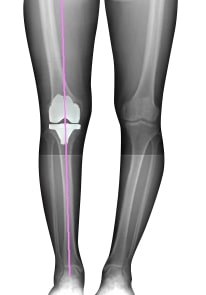

In knee replacement surgery, the arthritic portion of the knee is removed and replaced by an artificial joint that form the new surfaces of the knee joint. During Robot assisted total knee replacement, Robotic Knee Replacement Surgeon uses computed tomography (CT) scans to build a 3D model of the patient’s knee. With that virtual model as guide, the surgeon then uses the robotic arm to make accurate bone cuts and insert the knee components precisely.

Precise cutting for sub-millimeter accuracy and optimum alignment: Robot reviews the data and cuts the bone precisely with respect to the dimensions of the implant decided during pre-surgery planning stage. Precise cutting serves the optimum result also provides the correct alignment of a patient’s leg axis with the sub-millimeter dimensional accuracy and precise cutting for the optimal surgical outcome.